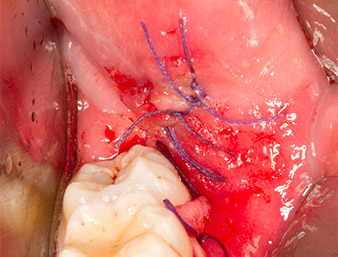

Successivamente, il tessuto osseo autogeno (Fig. 13) è stato posizionato nell'alveolo e nel circostante difetto osseo (Fig. 14). Un vello di collagene ricopriva i frammenti di osso fino a livello dell'osso come protezione per il nervo esposto (Fig. 15). Per chiudere il tessuto molle aperto sono state utilizzate suture con filo in Vicryl, USP 4.0 (Fig. 16). Dopo l'operazione sono stati prescritti una preparazione di Ibuprofene (Seractil 400 mg, 3x1) e un antibiotico costituito da amossicillina e acido clavulanico (Augmentin 1 g, 2x1).

La ferita si è cicatrizzata senza complicazioni (Fig. 17) e le suture sono state rimosse dopo sette giorni. Il paziente ha segnalato il ritorno della normale sensibilità. Non si è più presentato alcun dolore.